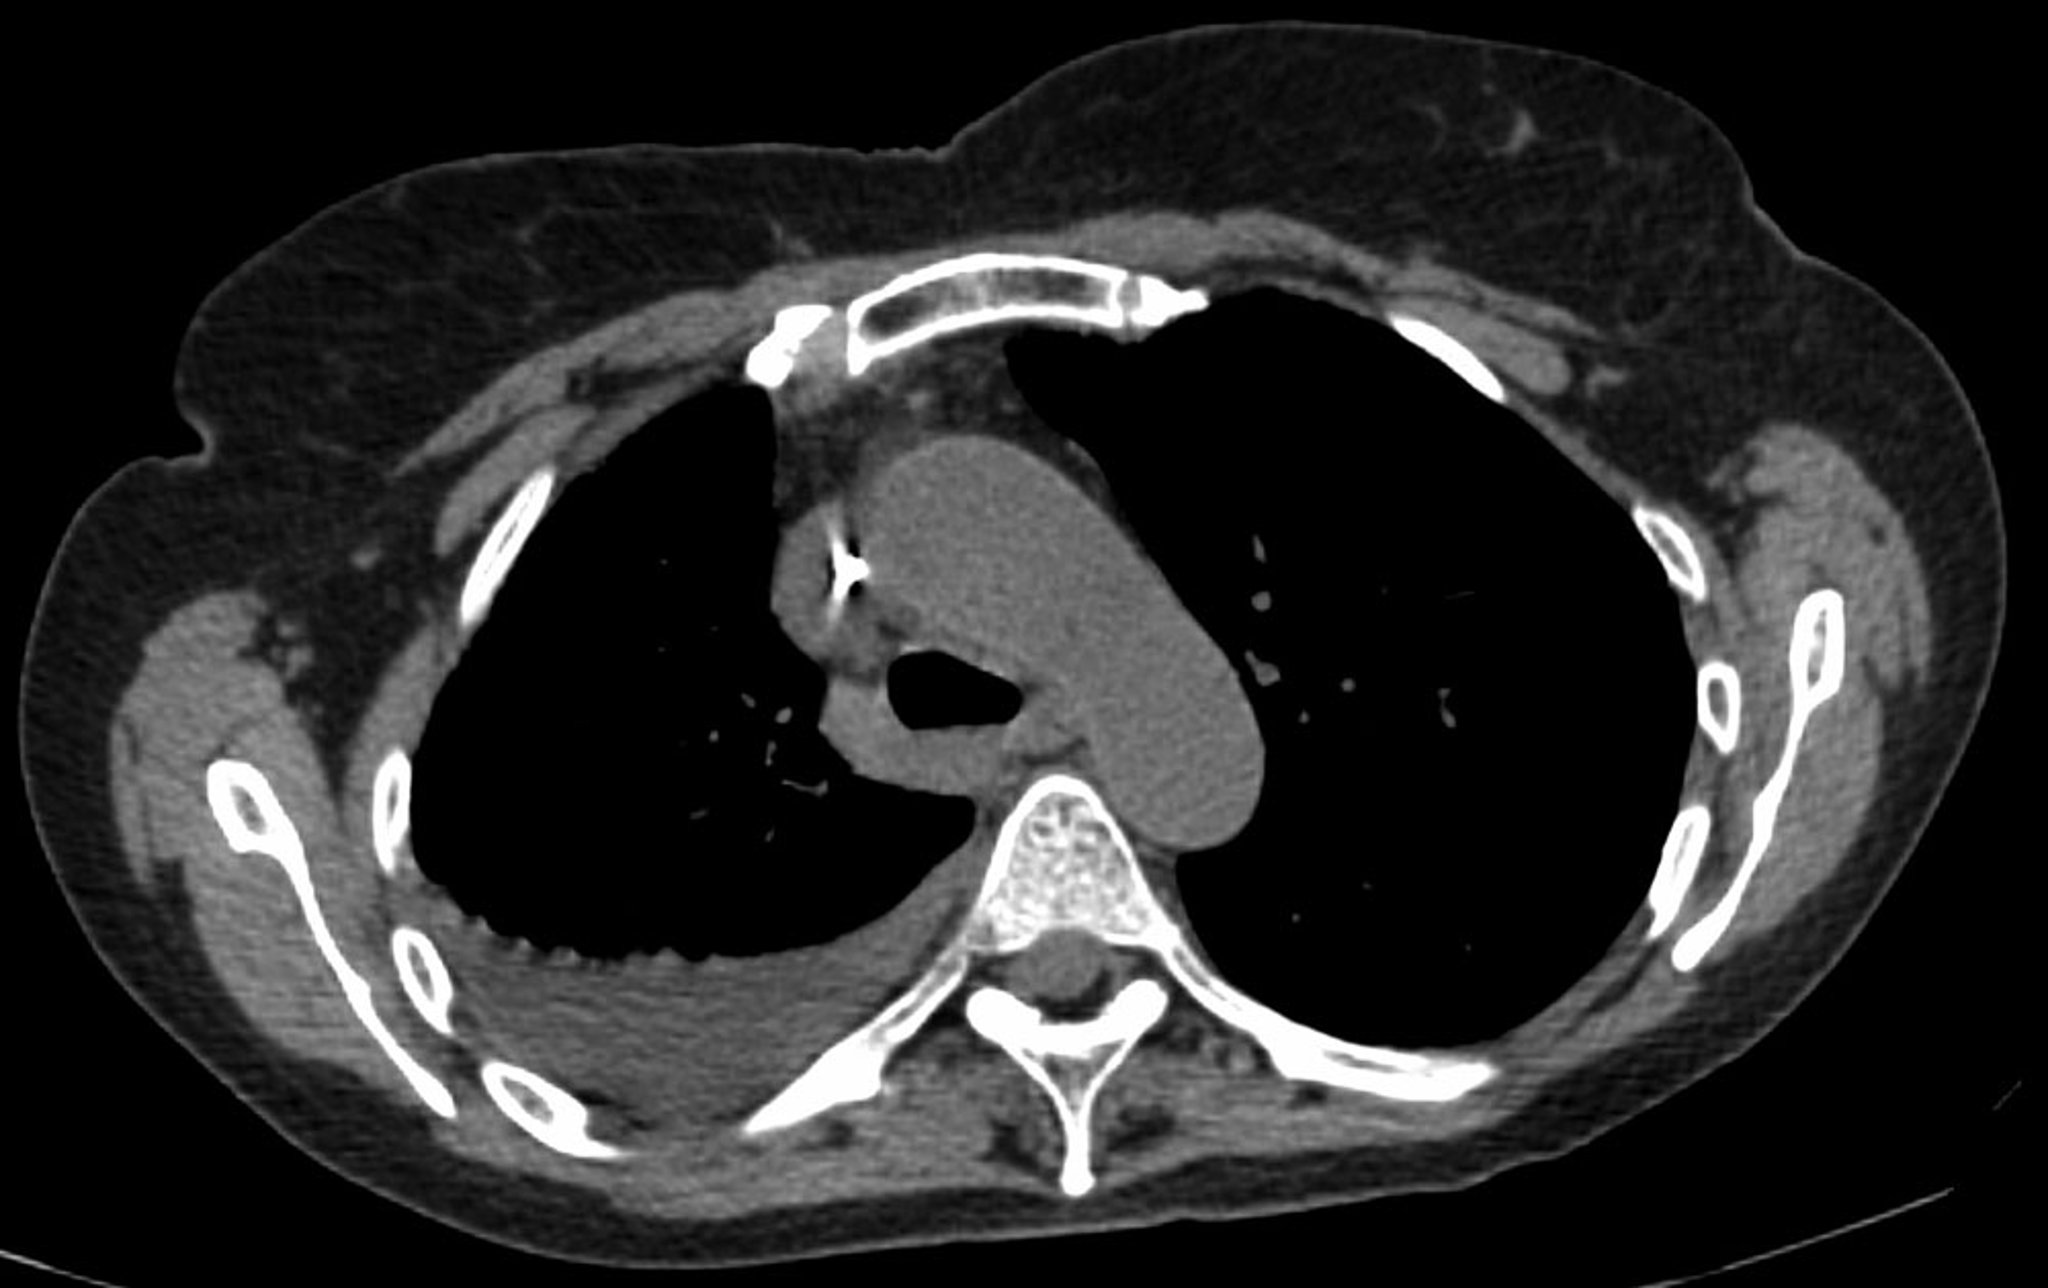

CT with venous contrast is a valuable next investigation that provides information on pleural enhancement and potential pleural nodularity. (Noncontrast CT may be used for initial evaluation but cannot exclude malignancy or infection.) CT with venous contrast is valuable for evaluating the underlying lung parenchyma for infiltrates or masses when the lung is obscured by the effusion or when the detail on chest radiographs is insufficient for distinguishing loculated fluid from a solid mass.

Imaging may also help. If the diagnosis remains unclear after pleural fluid analysis, CT with venous contrast enhancement is indicated to assess for pleural enhancement, pleural nodularity, pulmonary infiltrates, or mediastinal lesions. CT pulmonary angiography can evaluate for a suspected pulmonary embolus. Findings of pulmonary emboli indicate the need for long-term anticoagulation. Pleural nodularity and thickening indicate the need for pleural biopsy (thoracoscopic or image guided). The presence of lung infiltrates or lesions, depending on suspected causes, may indicate the need for bronchoscopy or image-guided lung biopsy.